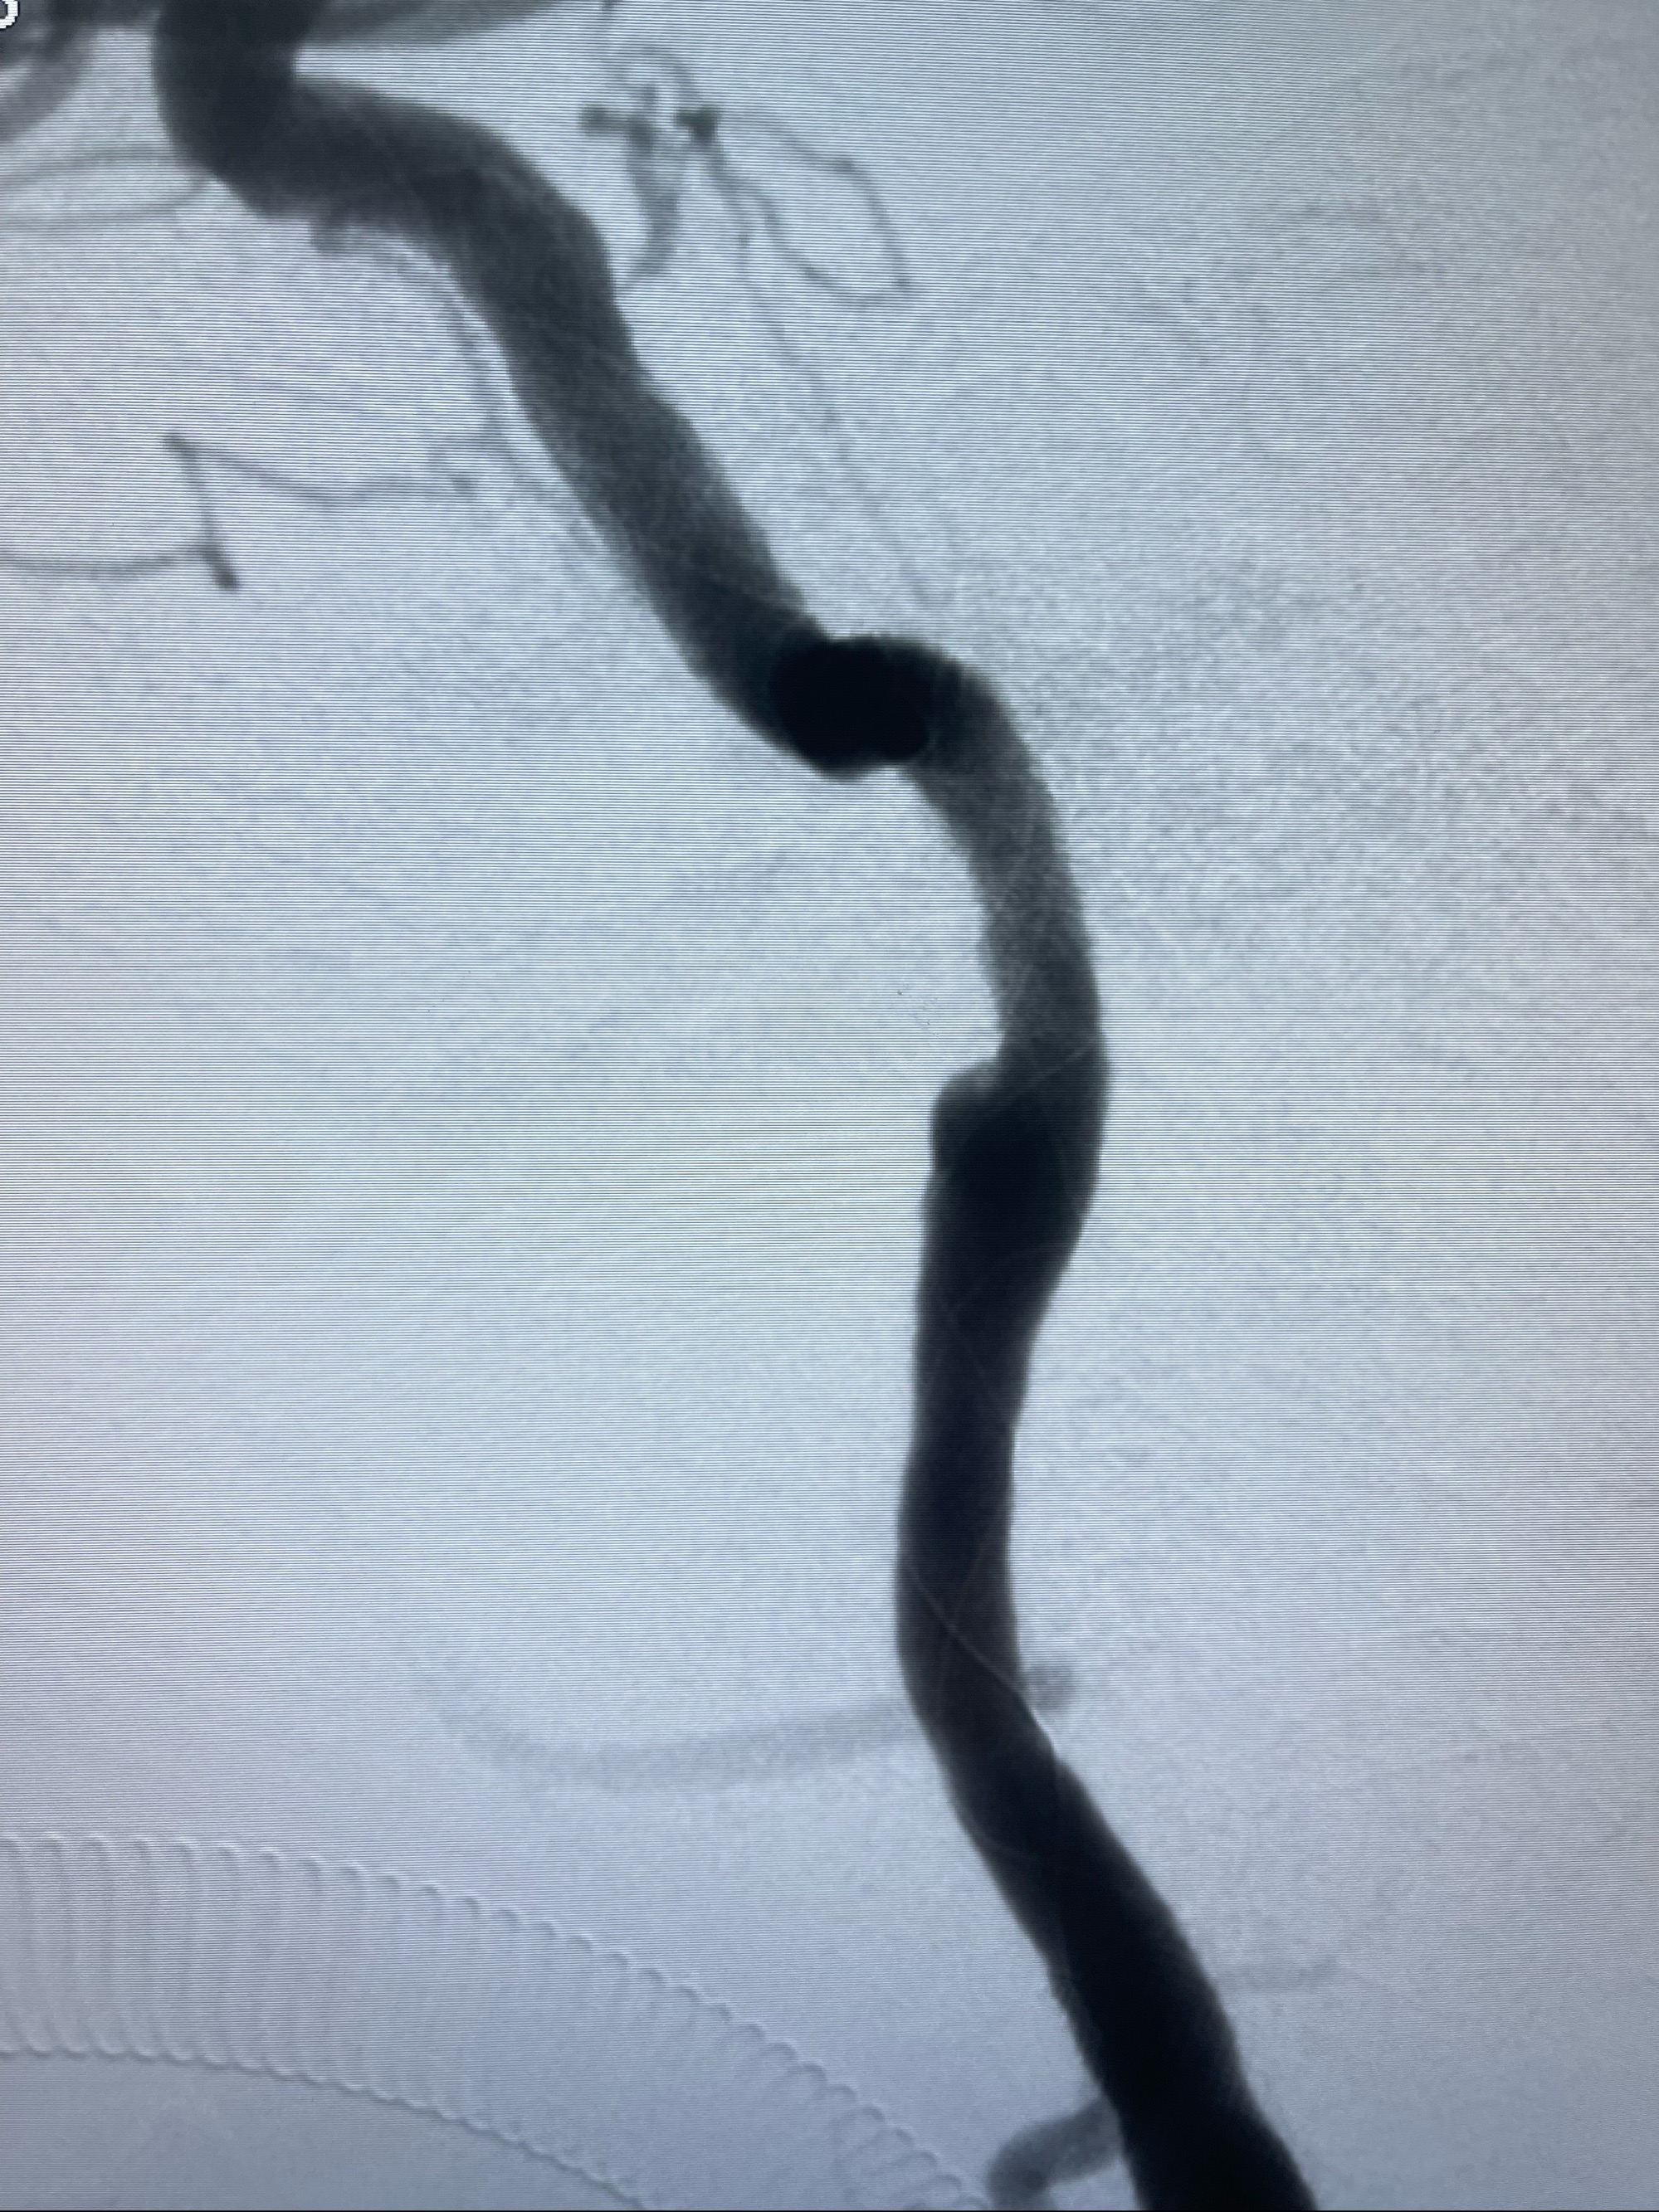

2023-07-10DSA:右侧颈内动脉岩骨段夹层伴中偏重度狭窄改变,左侧颈总动脉闭塞、右侧颈外动脉由右侧肋颈干甲颈干吻合代偿

箭头所示为颈内动脉岩骨段重度狭窄,结合MRI,考虑为肿瘤侵犯右侧颈内动脉

箭头以近至支架段管腔不规则狭窄

左侧颈总动脉起始段至分叉部闭塞,起始部呈现子弹头样改变

经导引导管造影显示支架远端颈内动脉不规则狭窄伴局部充盈缺损,同时行全身肝素化5ml